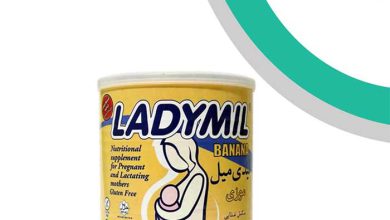

مکمل غذایی لیدی میل چیست؟ قیمت و 4 سایت برتر خرید

مکملهای غذایی به عنوان بخشی جداییناپذیر از رژیم غذایی مدرن، محصولاتی هستند که برای جبران کمبودهای تغذیهای بدن طراحی…